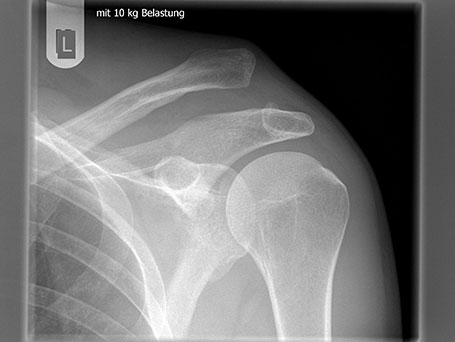

SCHULTERECKGELENKSSPRENGUNG

Die Schultereckgelenkssprengung ist eine Verletzung des Bandapparates der das Schlüsselbein mit dem Schulterblatt verbindet. Das Schlüsselbein wird aus seiner Verankerung herausgerissen und steht meist optisch sichtbar seitlich hoch. Die Verletzung wird in 6 verschiedene Grade eingeteilt (Rookwood Klassifikation).

Das Ausmaß der Verletzung wird durch eine klinische Untersuchung und Röntgenbilder erfasst. Die geringgradigen Verletzungen können konservativ behandelt werden (Rookwood I und II Verletzungen). Die höhergradigen Verletzungen (Rookwood IV – VI) werden zumeist operativ behandelt.  Bei der Rookwood III Verletzung (Hochstand der Clavicula um Schaftbreite) sollte nach einer horizontalen Instabilität gesucht werden (Typ IIIb). Dieser sollte eher operativ behandelt werden. Neuere Untersuchungen haben gezeigt, dass der Typ Rookwood III a konservativ gleich gute Ergebnisse wie operativ erzielt.

SCHULTERECKGELENKSSPRENGUNG IM RÖNTGENBILD

Bild von Schultereckgelenkssprengung